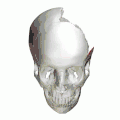

-

Animation. Left parietal bone removed. Squamosal sutures shown in red. -